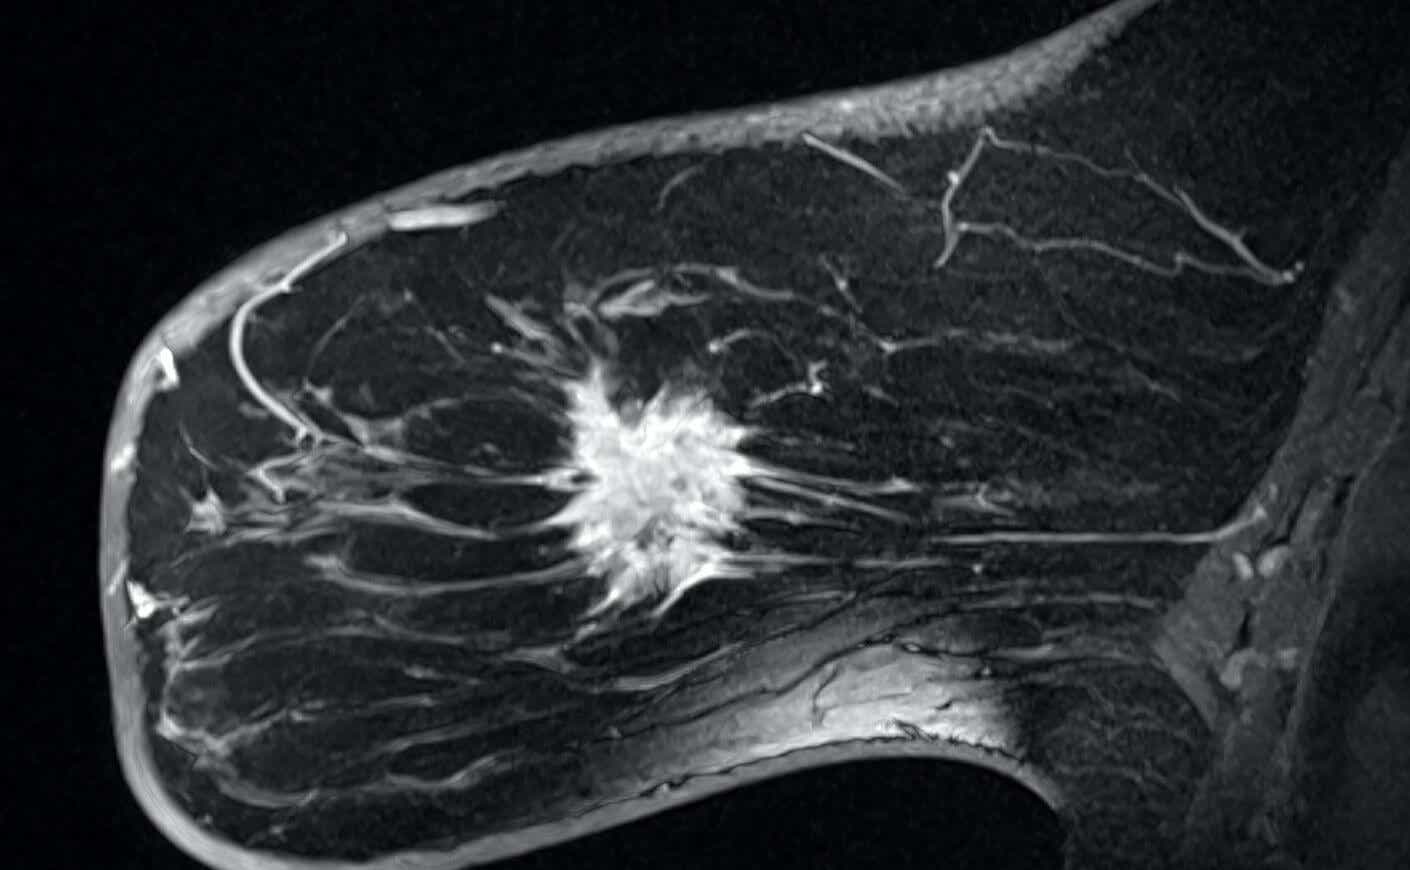

Using high-powered microscopes and complex computer algorithms, they diagram each stage in the development of breast cancer: from the first sign of cell mutation to the formation of tiny clusters, well before they are large enough to be considered tumors.

In late 2024, Dr. Brugge and her colleagues identified specific cells in breast tissue that contain the genetic seeds of breast tumors.

And they discovered that these “seed cells” are surprisingly common. In fact, they are present in the normal, healthy tissue of every breast sample her lab has examined, Dr. Brugge said, including samples from patients who haven’t had breast cancer but have had surgery for other reasons, such as breast reduction or a biopsy that proved benign.

The next research challenge for Dr. Brugge’s lab is clear: Find ways to detect, isolate, and terminate the mutant cells before they can spread and form tumors.